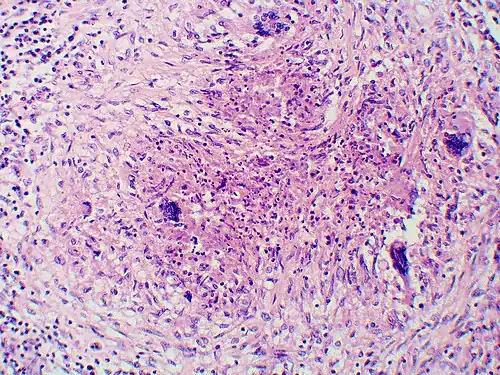

Granuloma with early suppuration. The fungal organisms are difficult to recognize at this low magnification. -